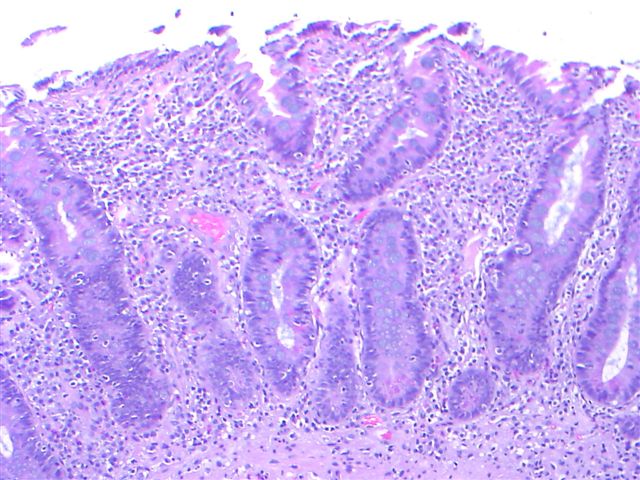

Microscopic (histologic) description

- Histological elementary lesions (Dig Liver Dis 2011;43:S385, Semin Diagn Pathol 2014;31:124):

- Increased intraepithelial T lymphocytes (IEL):

- 25 - 29 IEL/100 enterocytes is considered borderline

- > 30 IEL/100 enterocytes represents a pathological lymphocytosis

- Decreased enterocyte height, flattening of enterocytes, intracytoplasmic vacuolation and reduction or absence of brush border are suggestive but not specific

- Crypt hyperplasia:

- Extension of the regenerative epithelial crypts associated with changes in the presence of more than 1 mitosis per crypt

- Villous atrophy:

- Decrease in villous height, normal villous:crypt ratio (3:1) until total disappearance of villi

- This assessment requires proper orientation of the biopsies

- Increased intraepithelial T lymphocytes (IEL):

- Diagnostic categories are based on these elementary lesions:

- Modified Marsh-Oberhuber classification of histologic findings in celiac disease

- Simplified systems (Corazza & Villanaci or Ensari), which may be more reproducible (Arch Pathol Lab Med 2010;134:826, Pathol Res Pract 2016;212:1174)

- Different grades of duodenal mucosal lesions:

- Grade A / type 1: increased intraepithelial lymphocytes but no villous atrophy

- Grade B1 / type 2: villi still present but shortened

- Grade B2 / type 3: complete villous atrophy

Microscopic (histologic) images